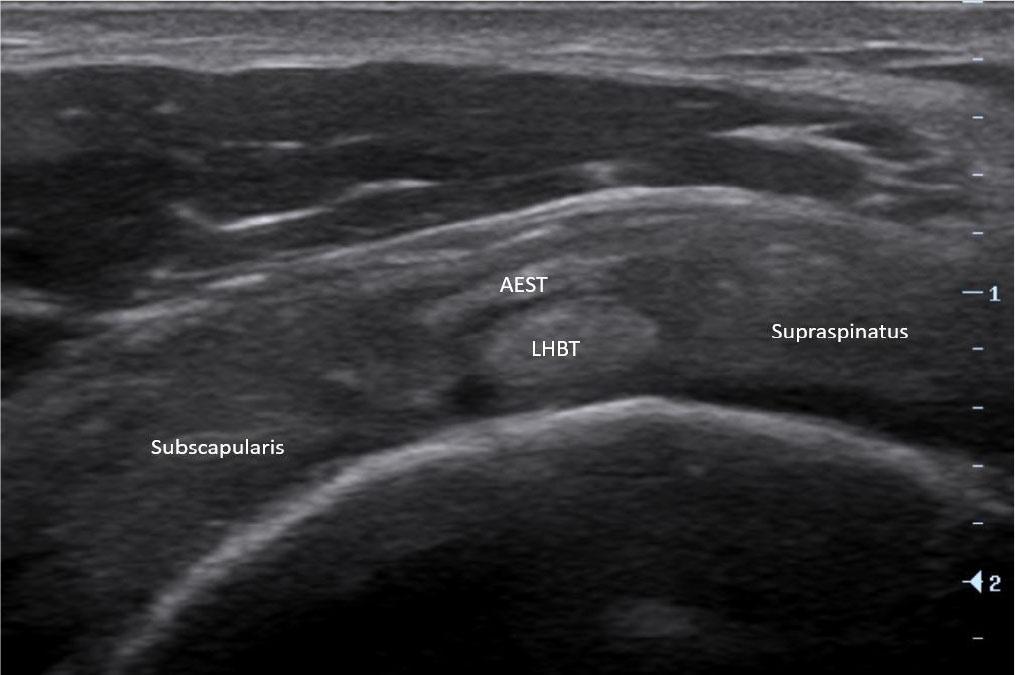

The aponeurotic expansion of the supraspinatus tendon (AEST) is an anatomical structure arising from the anterolateral aspect of the supraspinatus tendon and extending toward the long head of the biceps tendon (LHBT) within the rotator interval (Fig. 1)(1,2,3,4). First described in cadaveric and imaging studies, AEST has been increasingly recognized in modern radiology as a potential source of diagnostic confusion, as it may mimic a bifid biceps tendon, an accessory tendon, or even a partial tear of the LHBT(3,5,6,7,8,9). With the advent of high-resolution ultrasound and MRI, awareness of AEST has grown; however, its sonographic identification remains challenging and is often overlooked or misinterpreted (Fig. 2)(3,5,10,11).

Ultrasound image showing normal aponeurotic expansion of supraspinatus tendon (AEST) anterolateral to the long head of the biceps tendon (LHBT) at the intertubercular groove

At the level of the rotator interval, AEST was assessed for echogenicity, intrasubstance tears, and its relationship to the LHBT and subscapularis tendon (Fig. 3), while the supraspinatus was checked for tear-related changes. AEST was then examined at the intertubercular groove to determine its position (intragroove, subluxation, dislocation, medial dislocation; Fig. 4), along with LHBT and subscapularis integrity. The remaining shoulder structures, including the other rotator cuff tendons and the glenohumeral and acromioclavicular joints, were systematically reviewed. The findings are summarized in Tab. 1.